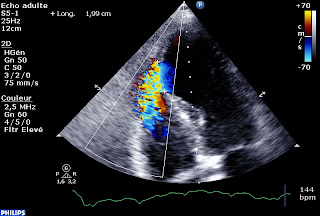

Heureusement, parfois l’echo, c’est simple. Un Infarctus semi récent compliqué d’un GROS œdème pulmonaire, un souffle en rayon de roue, et une rupture septale: